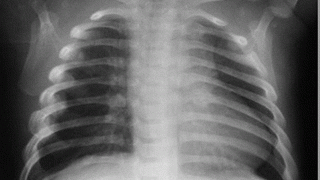

Инцидент произошел в минувшую субботу около 6.00. Пострадавшего доставили из дома по улице Полтавская в 1-ю горбольницу. Ему диагностировали – множественные переломы ребер.